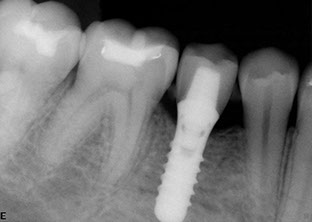

Dental implants have been used for decades to provide a stable support for missing teeth. Implants can be used to stabilize dentures, act as anchors for a bridge, or replace single teeth that are missing.

Implants are designed to be incorporated into the structure of the jawbone. A crown is then attached to the implant to function as a normal tooth. In most cases, implants take several months from placement to the final restoration(s). There is a period of healing while the implant becomes part of the body and stabilizes.